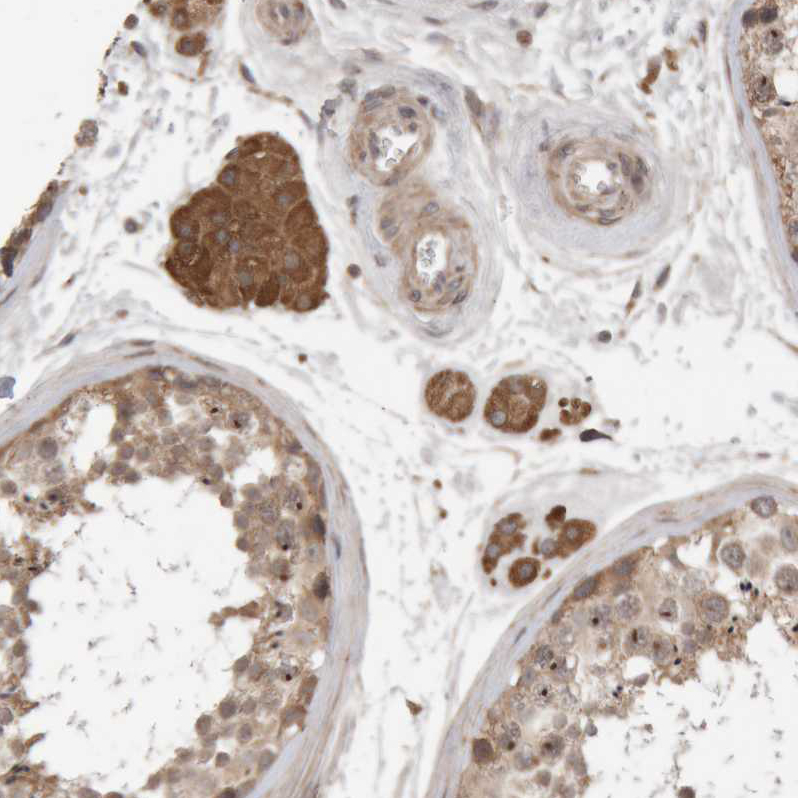

Immunohistochemical staining of human cerebral cortex shows moderate to strong cytoplasmic positivity in neurons.